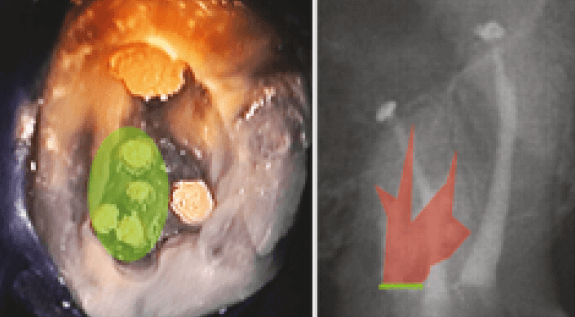

La paciente recibió anestesia local al 2% de lidocaína con 1:100.000 epinefrina. Se realizó aislamiento absoluto con dique de goma y se procedió a realizar apertura de cámara con fresa redonda de carburo Nº 4 (Jota, Rüthi, Suiza) y posterior delimitación y conformación de apertura de cámara con fresa Endo Z (Denstply Maillefer, Ballaigues, Suiza), se ubicaron los conductos disto-vestibular (DV) y palatino (P) con un explorador endodóntico DG-16; a nivel de la raíz MV dicho conducto no se encontraba permeable, situación que determinó la necesidad de exploración del piso de la cámara pulpar con microscopio óptico operatorio 2,19 marca DFVasconcellos (Canteiro-Valença/ RJ, Brasil). A la magnificación a 5X e intensa iluminación y siguiendo los principios propuestos por Krasner y Rankow 25, se observó entrada del conducto MV1 y 2 invaginaciones del piso de la cámara pulpar, las cuales siguen la línea de desarrollo en sentido del conducto MV al P (obliterada la entrada de los 3 conductos MV1, MV3, MV4), a su vez se determinó presencia de estructura de pared dentinaria mesial a los conductos MV1 y MV3.

La permeabilización de conductos obliterados de la raíz MV (MV1, MV3, MV4) y el MV2 se realizó con puntas ultrasónicas modelo CAP2 (Satelec/Acteon, Merignac, Francia) 2,19, limas K Nº 08 y 10 y ensanchado con lima K Nº 15 y 20 (Dentsply Maillefer, Ballaigues, Suiza), y microscopio operatorio, pudiendo permeabilizar todos los conductos (Figura 2); se obtuvo la conductometría con localizador apical MiniSybron Endo (Orange, California) 2; y confirmación radiográfica de longitud de trabajo (Figura 3). Se realizó preparación manual con limas de acero inoxidable y técnica Corono-Apical realizada únicamente con instrumental manual, irrigación del SCR con NaOCl (5 ml), seguido de solución fisiológica (5 ml), EDTA al 17% (3 ml), solución fisiológica (5 ml), e irrigación final de clorhexidina al 2% (5 ml) 26, medicación intraconductos con Hidróxido de Calcio (Ultracal, Ultradent, Utah, USA), y obturación con ionómero de vidrio (LC Fuji II, GC América INC, USA).

Figura 2. Imagen clínica a 5X de magnificación (a) y dibujo esquemático de localización de conductos (b).

Figura 3. Rx Conductometría

En el presente caso la utilización de microscopio óptico operatorio junto con la toma de radiografías, durante el desarrollo de la terapia endodóntica, ayudaron a entender la compleja variación anatómica del SCR, confirmando la presencia de 6 conductos radiculares (4 conductos en la raíz MV, 1 en la raíz DV y 1 en la raíz P). Figura 6.

Figura 6. a) Imagen clínica a 5X magnificación de obturación del SCR. b) Rx de obturación definitiva y representación esquemática de configuración de conductos en raíz MV (color rojo).